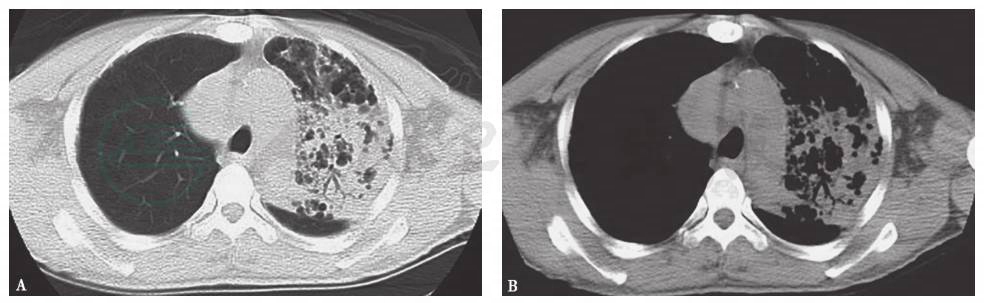

金黄色葡萄球菌包括甲氧西林敏感性(MSSA)和耐甲氧西林金黄色葡萄球菌(MRSA),均可引起社区获得性感染。MRSA常引起皮肤和软组织感染坏死,因其可产生杀白细胞素(panto-valentine,PVL),破坏白细胞,导致外周血白细胞水平下降及肺组织坏死。因此,若MRSA引起肺部感染,常较为严重,且感染发展迅速,以坏死性肺炎和脓胸为主,可有高热、咳脓痰甚至脓毒症休克等临床表现(图4)。从现有临床资料来看,本病例并不符合MRSA所致肺部感染表现。广泛耐药或全耐药革兰阴性杆菌引起的感染多为院内获得性因素,本例患者既无基础肺病病史,也无院内获得性感染的机会和环境,因此广泛耐药或全耐药大肠杆菌或肺炎克雷伯菌感染的可能性很小。

病毒也是导致成年人社区获性肺炎的一种常见病原体。流感病毒、鼻病毒、腺病毒和呼吸道合胞病毒等引起感染者,外周血白细胞多为正常或降低。而且,病毒性肺炎可以从初始的单叶段病灶很快发展为多叶段受累,但很少发生肺组织坏死和气囊样改变(图5);要么短期内病情迅速加重,发展为重症肺炎,甚至急性呼吸窘迫综合征(ARDS),要么呈自限性,逐渐好转,很少呈迁延状态或亚急性过程。本病例与上述情况不符,故由病毒引起肺部感染的可能性很小。

图4 社区获得性MRSA肺炎胸部X线表现

男性患者,28岁,发热、咳嗽、咳痰、胸痛,胸部X线可见右上肺大片实变影,诊断为社区获得性MRSA肺炎。

图5 甲型H1N1流感病毒性肺炎胸部CT表现

胸部CT可见双肺多叶段大片磨玻璃高密度和实变影,右肺更明显